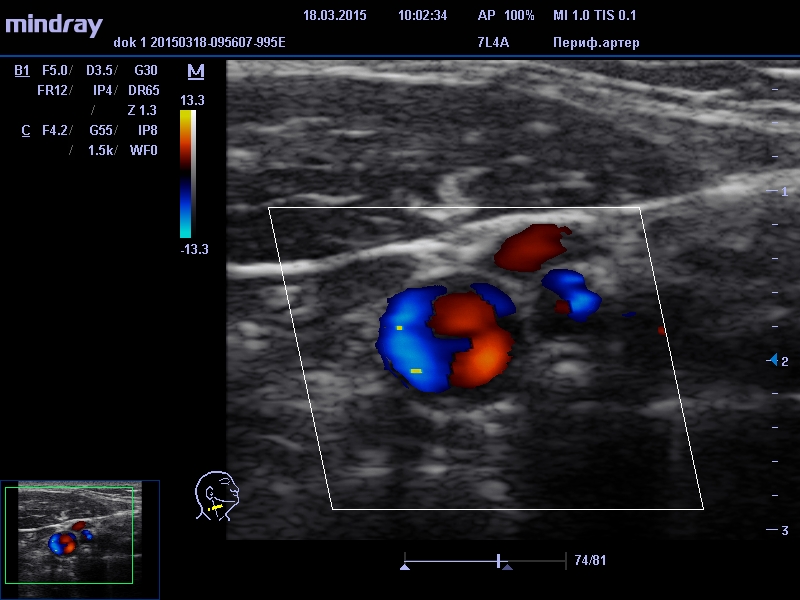

В это время на мониторе УЗИ сканера появляется изображение сосудов в разных режимах работы прибора. Диагност определяет толщину стенок, сужение или расширение участков сосудов, состояние их просветов (наличие атеросклеротических бляшек, а также возможных тромбов, их форму и размеры), имеются ли изгибы сосудов и их степень выраженности, аномалии развития. Большое значение имеет определение интенсивности кровотока и наличие нарушений кровообращения в определенных отделах головного мозга.